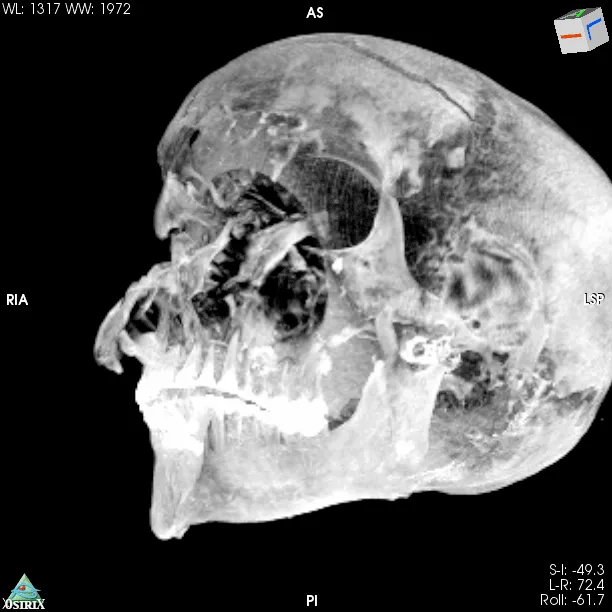

A CT scan study of the mummy of Pharaoh Seqenenre-Taa-II, an Egyptian ruler whose death eventually helped reunite the kingdom, revealed new details about how the king died. A recent paper suggests that the pharaoh died close to the battlefield and was ceremoniously executed by several people using Hyksos weapons. Additionally, the computer-processed x-rays revealed his embalmers had skillfully concealed some of the wounds, implying professional mummification of the body, despite its poor preservation.

But computed tomography (CT) scans of the mummified remains of Seqenenre revealed new details about his head injuries, including previously undetected lesions that embalmers had skillfully concealed.

The authors of the new paper offer a novel interpretation of the events before and after the king’s death based on the computer-processed x-ray images: Seqenenre had indeed been captured on the battlefield, but his hands had been tied behind his back, preventing him from defending against the attack.

For example, the CT scans, combined with other evidence, suggest the execution had been carried out by multiple attackers, which the scientists confirmed by studying five different Hyksos weapons that matched the king’s wounds.

The CT study also determined that Seqenenre was about 40 when he died, based on the detailed morphology revealed in the images, providing the most precise estimate to date.

In addition, the CT study revealed important details about the mummification of Seqenenre’s body. For instance, the embalmers used a sophisticated method to hide the king’s head wounds under a layer of embalming material that functioned similarly to the fillers used in modern plastic surgery. This would imply that mummification took place in a real mummification laboratory rather than in a poorly equipped place, as previously interpreted.